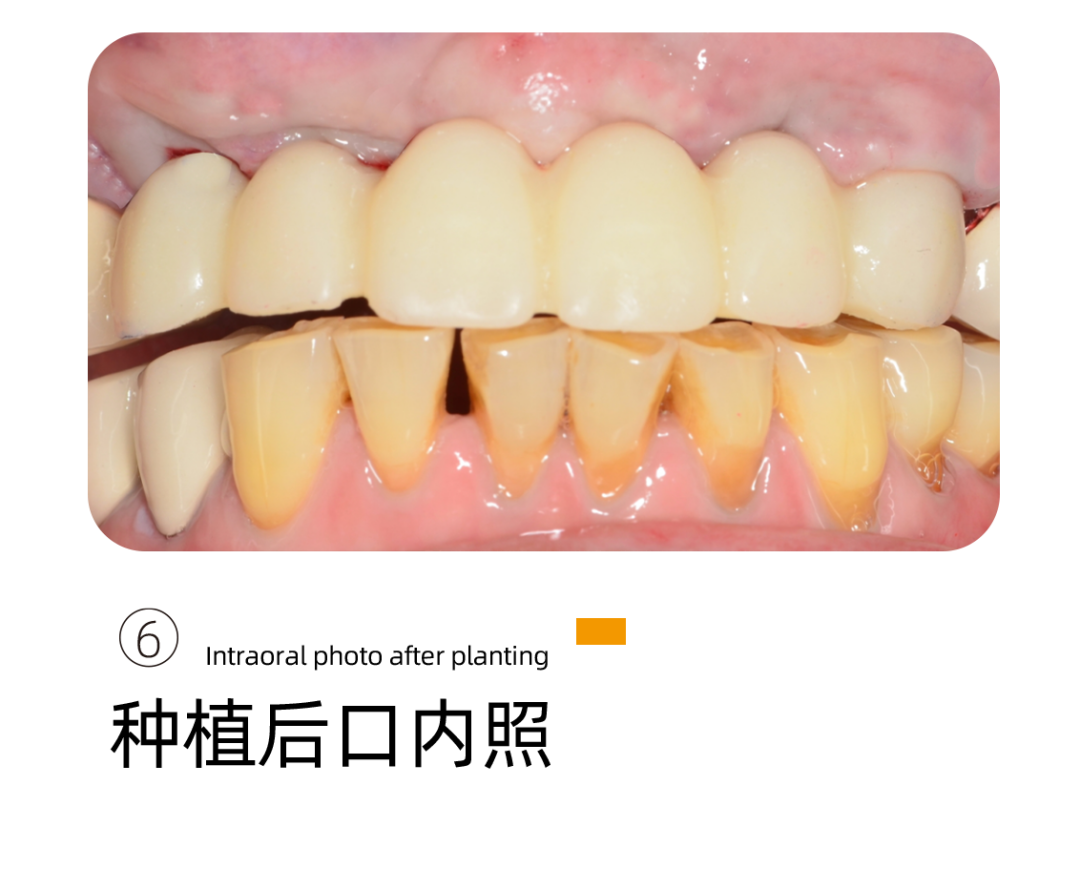

这是阿姨来找李雪松院长看牙最开始的样子。

不是这样的图片,我们都没有办法理解这样的口腔情况对一个老人来说意味着什么。阿姨说的吃东西靠吞不是被夸大的感受,而是她每天的日常。

下牙种植完成后,阿姨的感受很好,基本没有疼痛感只有稍微的不适应,重新找回的牙齿让阿姨多了很多生活的幸福。

当天,阿姨就带上了牙 ,恢复了咀嚼的功能。

细致又专业,在手术的过程中注重交流,注重细节,”手很轻“。种植当天就可以吃东西,找回了久违的幸福。